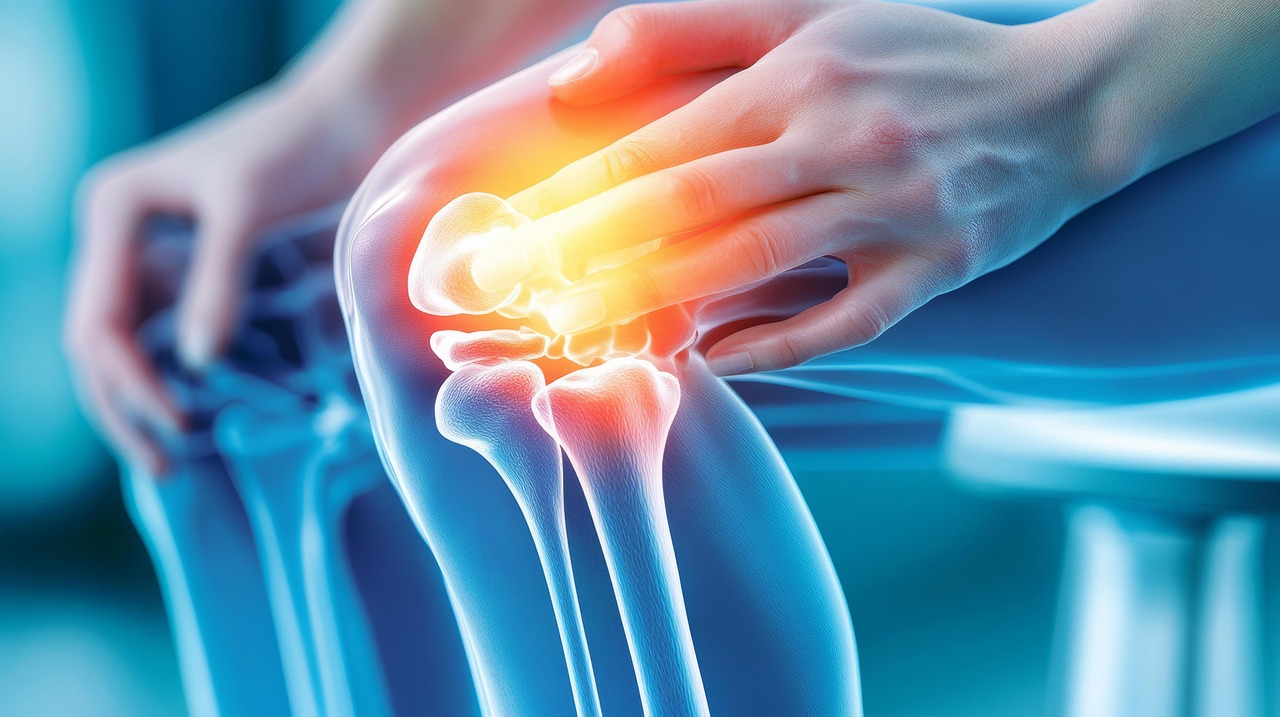

- 퇴행성 관절염: 연골이 점점 닳아 없어지면서, 뼈끼리 직접 마찰하며 통증 유발

이런 증상이 반복된다면 위험 신호입니다

- 무릎을 굽히거나 펼 때 ‘뚝뚝’ 소리가 남

- 오래 앉아 있다 일어나면 무릎이 뻣뻣하고 욱신거림

- 계단을 내려갈 때 더 아픔

- 무릎이 붓고, 열이 나는 경우도 있음

2주 이상 통증 지속 시 반드시 병원 진료가 필요합니다.